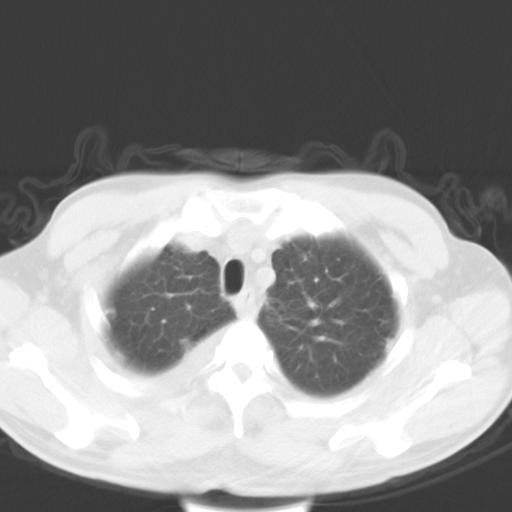

以下是引用zjzjr在2010-3-21 17:39:00的发言:[br]右下中心型肺癌并阻塞性肺炎/不张,纵膈淋巴结肿大,右侧大量胸腔积液,左侧少量胸腔积液

以下是引用zxl51642在2010-3-21 17:06:00的发言:[br]右下中心型肺癌并阻塞性肺炎/不张,纵膈淋巴结肿大,右侧大量胸腔积液,左侧少量胸腔积液,少量腹水。建议纤维支气管镜进一步检查。